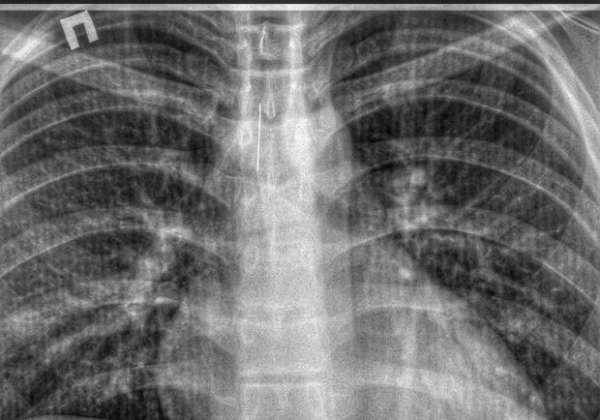

В Одесской области врачи вытащили из трахеи подростка иголку. Фото: facebook.com/KNPBDMBL

В городе Белгород-Днестровский из трахеи подростка вытащили иголку.

Так, 2 февраля в приемное отделение городской больницы из одного из районных поселков городского типа доставили подростка. В трахее пациента обнаружили постороннее тело – иголку длиной в четыре сантиметра.

В Одесской области врачи вытащили из трахеи подростка иголку. Фото: facebook.com/KNPBDMBL

Инородный предмет изъяли эндоскопическим методом.

На данный момент пациент чувствует себя удовлетворительно и находится под присмотром медицинского персонала в хирургическом отделении.